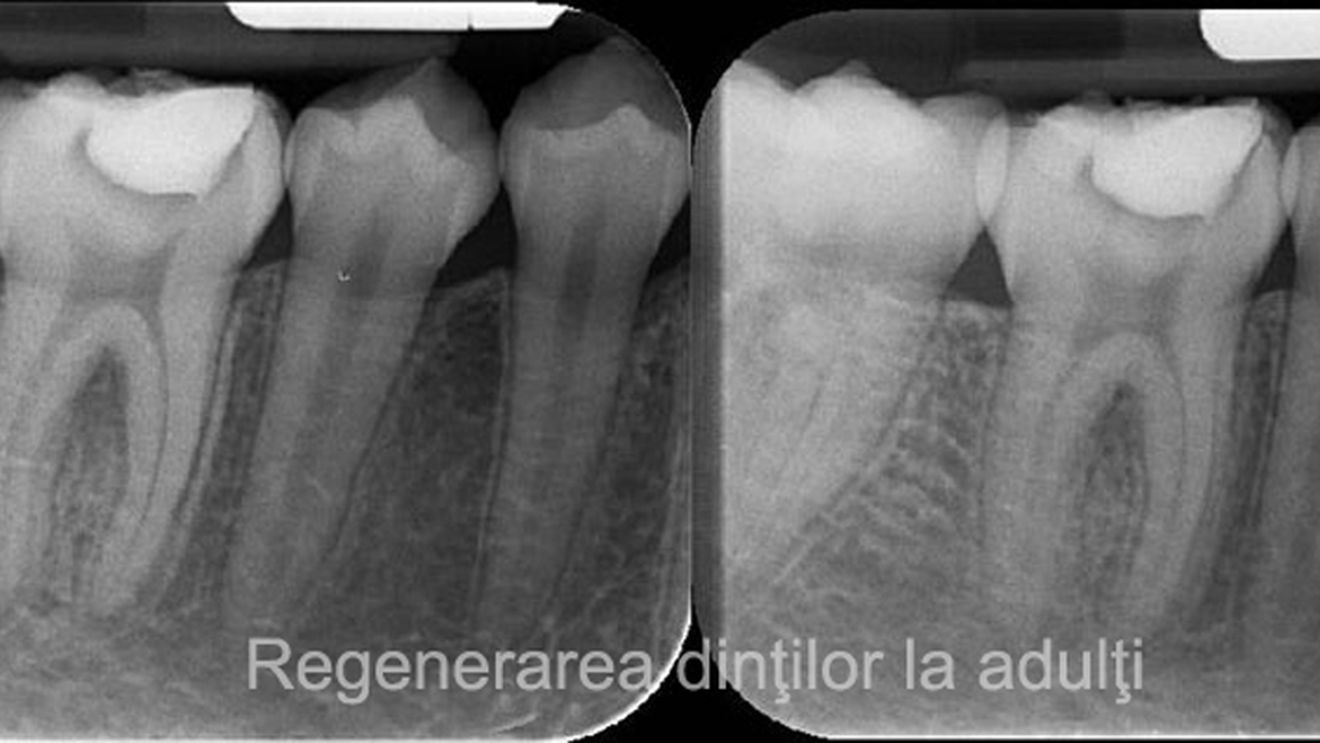

Deși pare contraintuitiv, un medicament folosit de pacienții ce suferă de boala Alzheimer are capacitatea de a regenera dinții utilizatorilor.

Dezvoltat și testat pentru a trata boala Alzheimer, medicamentul se întâmplă, de asemenea, să ajute mecanismul natural de regenerare a dinților. Tideglusib funcționează prin stimularea celulelor stem din pulpa dinților, sursa de dentină nouă. Dentina este substanța mineralizată sub smalțul dintelui și distrusă de cariile dentare.

Dinții pot regenera în mod natural dentina, fără asistență, dar numai în anumite circumstanțe. Pulpa trebuie expusă prin infecție, cum ar fi degradarea, sau traume pentru a determina fabricarea dentinei. Dar chiar și atunci, dintele poate să redea doar un strat foarte subțire (nu este suficient pentru a repara cavitățile cauzate de carii, care sunt în general adânci). Tideglusib modifică acest rezultat, deoarece împiedică GSK-3, care oprește formarea dentinei.

O echipă de cercetători a testat medicamentul pe șoareci, tratând cariile acestora cu un burete de colegan biodegradabil, îmbibat in tideglusib. În timp, buretele s-a dezintegrat, fiind înlocuit de dentină, dintele reparându-se de la sine. Deoarece această metodă încurajează corpul să se vindece singur, poate să elimine o mulțime din problemele legate de tehnicile actuale.